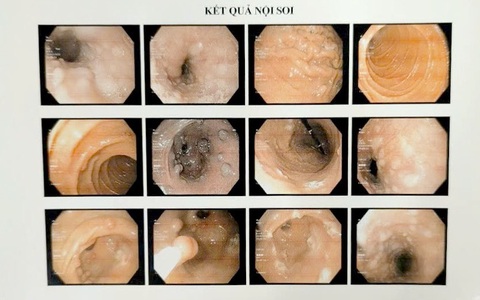

Hầu hết bệnh nhân mắc Cowden syndrome đều phát triển các polyp tại đường tiêu hóa trên và ở đại trực tràng và nguy cơ tiến triển thành ung thư đại trực tràng tăng lên đáng kể. Trên da của người bệnh cũng xuất hiện nhiều bất thường khi người bệnh ngoài 20 tuổi như: U nhú, các u lành tính.